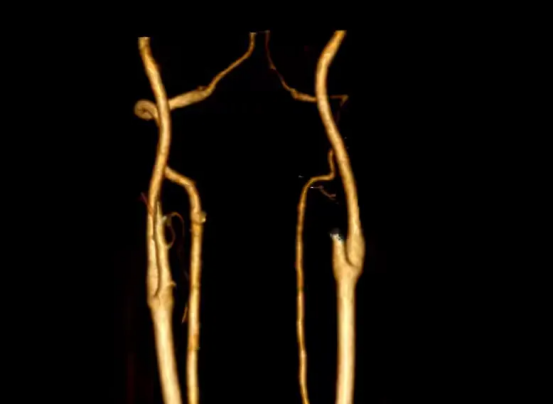

患者行脑血管造影显示左侧椎动脉夹层已修复

为进一步明确夹层的位置、长度以及血流情况并进一步治疗,脑五科团队为患者进行脑血管造影检查明确为椎动脉夹层,血流良好,不需要血管内治疗。经积极抗凝等治疗,宋先生头晕及双下肢无力等症状基本消失。